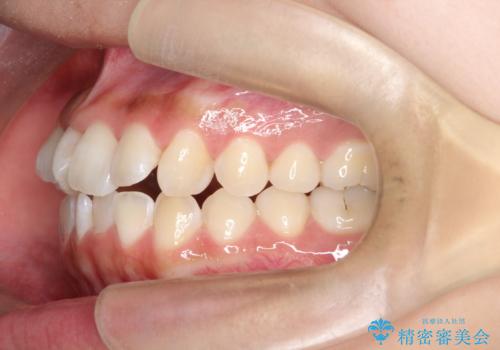

翼状捻転と叢生を矯正で改善

- 治療計画

治療では、審美ワイヤーを使用し、目立ちにくく配慮しながら矯正を進めました。上顎にリンガルアーチと矯正用アンカースクリューを用いて臼歯部を安定的に遠心移動させ、歯列全体のスペースを確保しました。その後、回転していた前歯を正しい位置に配列し、全体的な歯並びの改善を行いました。治療中は、装置の適切な管理と口腔衛生を徹底することが重要でした。結果として、見た目だけでなく機能的にも優れた歯列を実現することができ、患者様にもご満足いただけました。